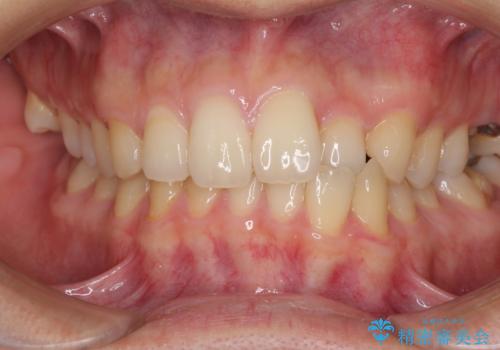

[ 矯正と補綴、総合歯科治療 ] クロスバイトを避ける前歯部審美ブリッジ

![[ 矯正と補綴、総合歯科治療 ] クロスバイトを避ける前歯部審美ブリッジの症例 治療前](https://seimitsushinbi.jp/wp/wp-content/uploads/2021/07/IMG_9914-500x350.jpg?v=1626697179)